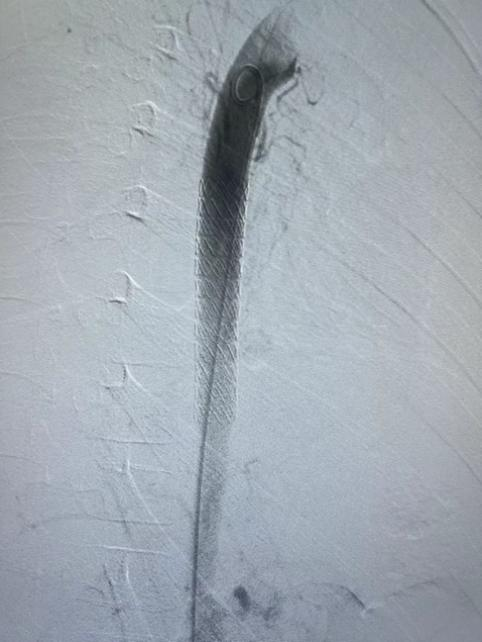

1.穿刺左侧股动脉,造影确定瘘口位置。

gore医疗怎么样How I Do It | 张雷杨教授团队:Gore VBX用于儿童主动脉食管瘘治疗一例分享_https://www.jmylbn.com_新闻资讯_第4张

2.根据术前测量患者降动脉9.2mm,选择11*59 mm Gore VBX 球扩覆膜支架,准确定位于后采用球囊扩张,将球囊充盈压到10 atm,将支架扩张至11mm。

3.支架释放后造影提示胸降主动脉局部假性动脉瘤和主动脉食管瘘消失,支架与主动脉贴附良好。